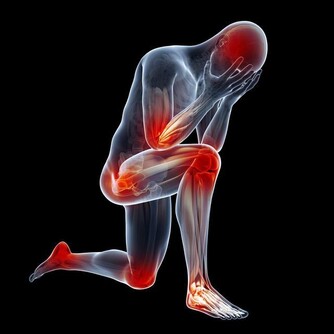

中醫裡有“六淫之氣”的說法,說的就是所有的疾病都因這六種邪氣所引發,分別是濕、風、寒、暑、火、燥、寒。其中濕邪的危害最大,有句俗話“一濕則百病生”說的就是它,不僅是它本身的危害大,它還能與其餘的邪氣相結合,最多人熟知的就是風濕和濕熱。

【濕氣重的危害】

濕氣所引起的疾病大致分為風濕類疾病、皮膚疾病、婦科疾病、胃腸道疾病、心腦血管疾病。會出現關節酸痛、頭暈胸悶、全身乏力、噁心乾嘔的症狀,嚴重的會影響女性的生理健康,引起嚴重的婦科疾病,例如月經不調、白帶異常、下陰瘙癢有異味等等。

身體的健康需要的不止上文的特徵,還需要避免這六淫之邪,濕氣在高危期的人裡影響最為之大,因為此時我們的免疫抵抗力波動是最大的,甚至是最低,濕邪影響的不只是我們的健康,還有可能影響到我們的壽命!所以祛濕是人人都需要的做的第一件事。